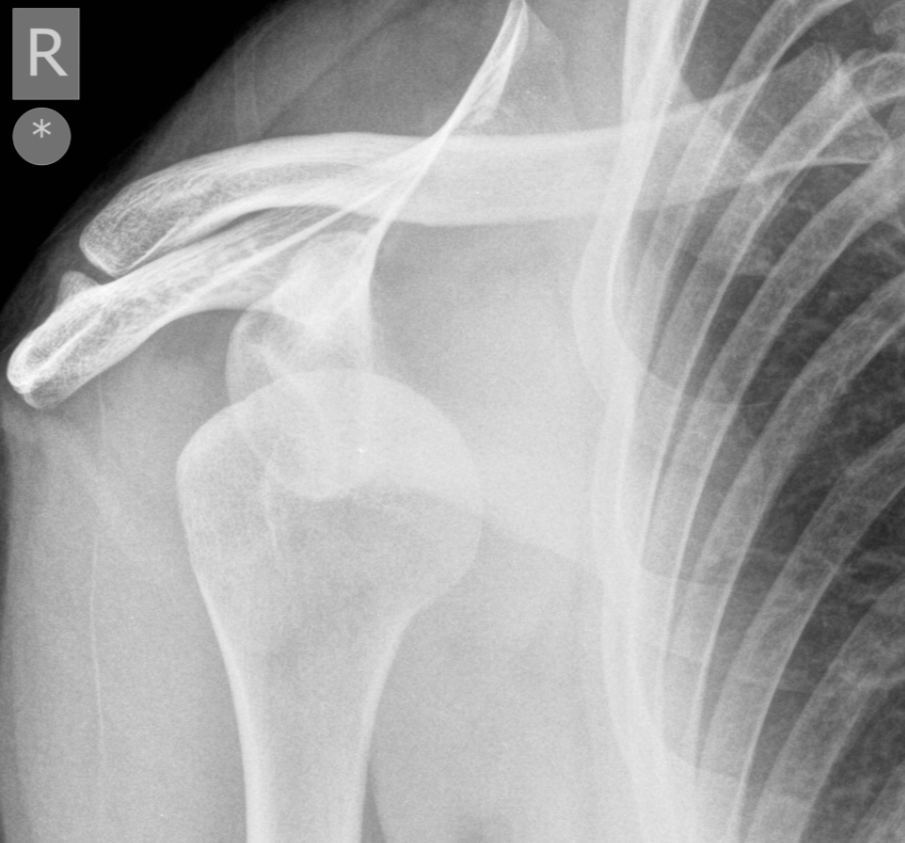

3. Anterior glenohumeral dislocation